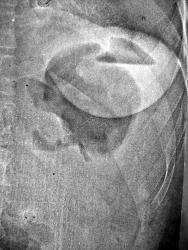

А хирурги надо мной посмеялись, ничего оперативного не предпренимали, назначили антибиотики, через неделю на контрольном снимке - уже ничего. Сказали, что клиники абсцесса не было, что то наподобие серомы... Больная благополучно выписана без повторных хирургических вмешательств...

Считаю, что рентгенданные не позволяют в этом случае исключить поддиафрагмальный абсцесс. Возникает вопрос: если с больным все в порядке, если у хирургов был повод посмеяться, то каким образом пациент оказался в рентгенкабинете? Профосмотр, или как? И почему назначили антибиотики?

После операций в брюшной полости на месте послеоперационной травмы обязательно скапливается какое-либо количество реактивного выпота. Кроме этого в бр. полости после лапаротоми обязательно остается и воздух. Так что встретить и жидкость и газ довольно легко... Вместе они дают формальную картину абсцесса, как в нашем случае... Но только в тех ситуациях, когда защитных сил организма не хватает и содержимое инфицируется - это реализуется в абсцесс. Типичная ситуация - после пульмонэктомии в гемитораксе скапливается до литра жидкости, но никто не говорит об абсцессе... Совершенно естественно, что такие скопления жидкости дают определенную клинику, а реакция хирургов с антибиотиками для профилактики, думаю, вполне понятна.

В рентгенологии не все так бывает однозначно. После этого наблюдения я встречал не менее десятка подобных случаев, и тот кто много работал с хирургами, я уверен, это подтвердит.